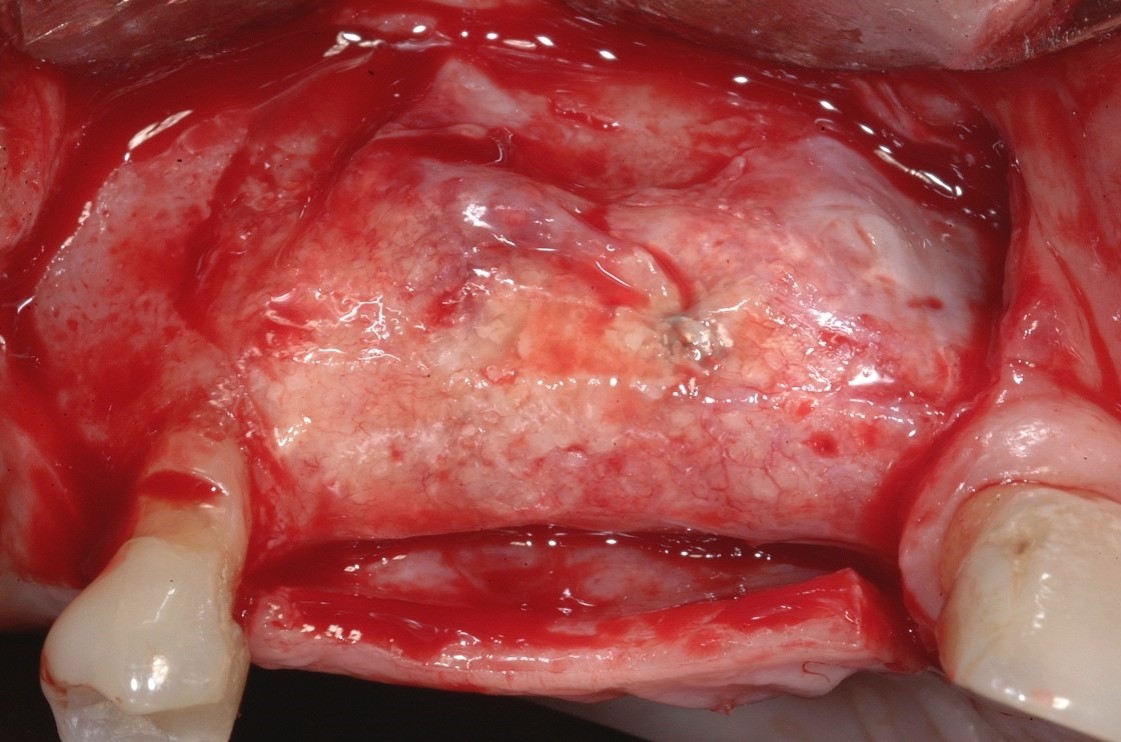

Fig 8. After the dense PTFE membrane and tacks were removed, good quality bone was observed.

Figure 8